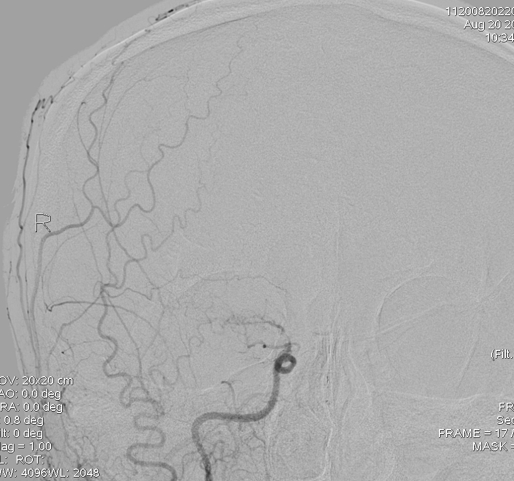

DSA显示右侧颈内动脉末端闭塞:

但是左侧是大脑中动脉闭塞: